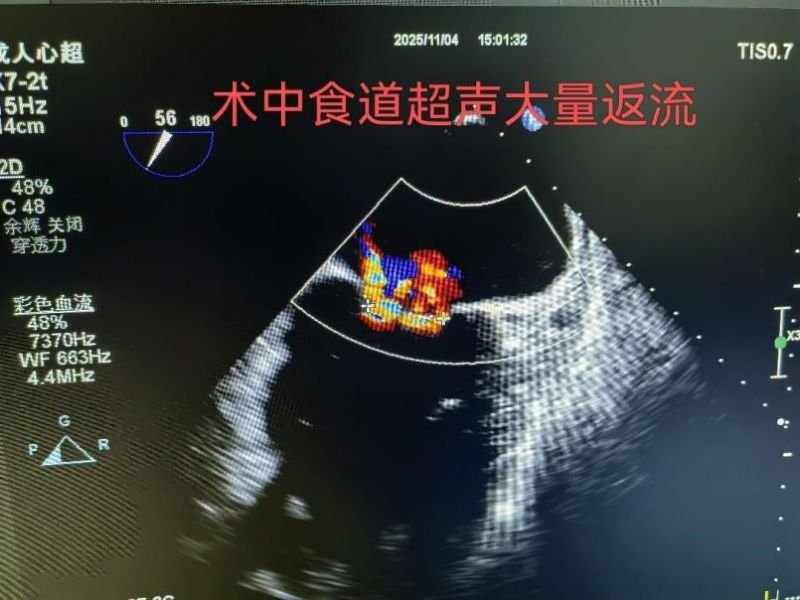

手术于11月4日下午进行,通过股静脉穿刺送入夹合器,在食道超声实时引导下,精准植入2枚瓣膜夹修复二尖瓣。整个过程历时约2小时,术中出血量仅50ml。术后次日,患者即可下床活动,复查显示EF提升至46%,二尖瓣返流面积缩小至3.0cm²,左心房缩小至66mm,胸闷、气短症状明显缓解。

2.精准定位:在食道超声和X线引导下,将夹合器送达二尖瓣位置,通过夹合病变瓣膜减少返流;